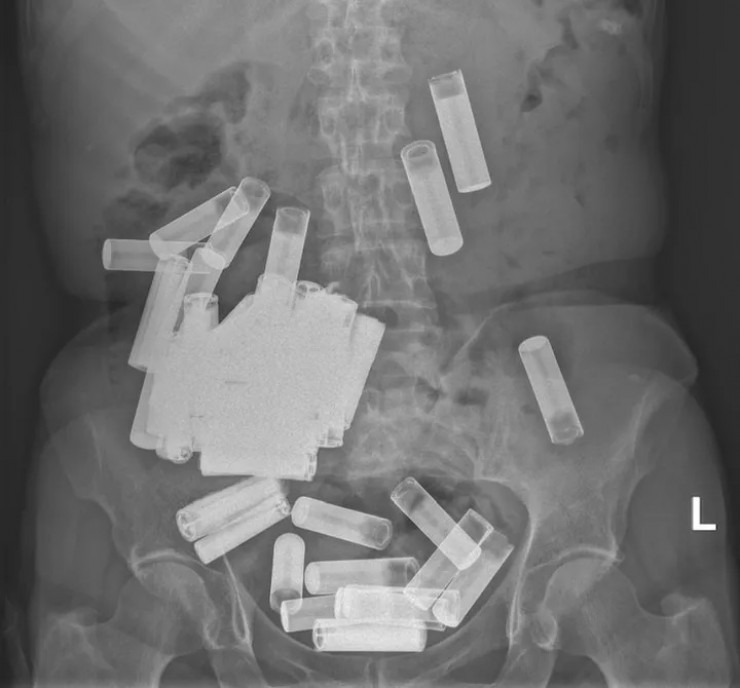

В Ирландии врачи вытащили из желудка и толстой кишки 66-летней пациентки 55 пальчиковых батареек, передает Tengrinews.kz со ссылкой на HuffPost.

Жительница Дублина обратилась в госпиталь Святого Винсента с жалобами на вздутие живота и боли. Медики сделали УЗИ и обнаружили в ее желудке и толстой кишке массу посторонних предметов.

Сначала медики решили подождать, пока инородные предметы выйдут из организма естественным путем, но спустя неделю тело покинули всего пять батареек, а боль в животе пациентки усилилась. Тогда врачи решили прооперировать женщину и извлекли из нее еще 50 пальчиковых батареек.

"Насколько нам известно, этот случай представляет собой самое большое зарегистрированное количество батареек, проглоченных в один момент времени", - говорится в статье.